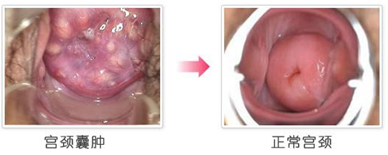

阴道镜检查

这种宫颈囊肿诊断方法直观明显,可以直接发现患病部位,诊断是否有不正常的病变,同时判定病灶的严重程度,做为治疗的依据。